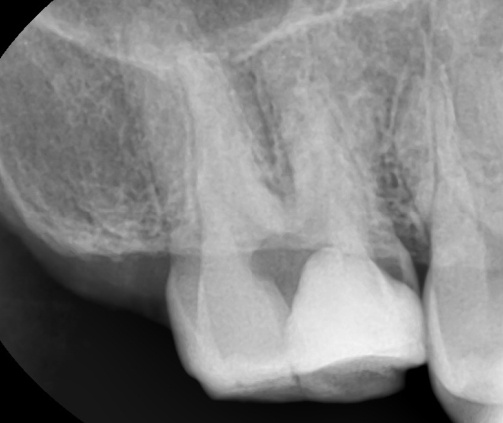

30대 환자가 어금니가 아프다는 Cheif Complaint (주관적인 증상호소)를 가지로 내원했습니다.

치과의사는 초능력자가 아니라서

투시력이 없다보니 기본적으로 처음 마주하기 전에 방사선 사진을 찍어서 보이지 않는 내부를 보게 됩니다.

위 사진 처럼 확연하게 치아가 검정색으로 보이는 경우에는

충치 진단기를 사용하지 않아도

매우 심하게 충치에 이환 되어 있다는 것을 알 수 있습니다.

위 사진의 경우 증상이 발생하였기 때문에 결국 신경치료를 들어갈 수 밖에 없는 신경감염이 발생했다는 것을 알 수 있습니다.